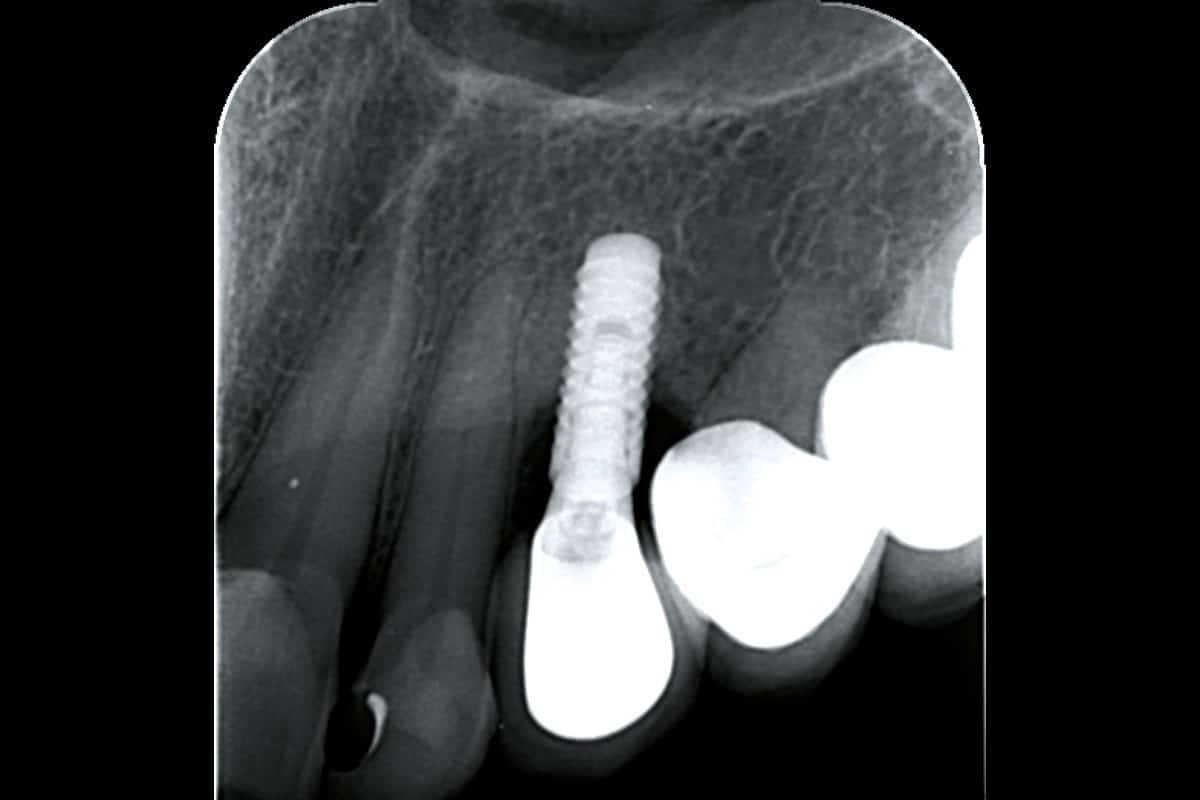

A patient presented with a peri-implant bone defect characterized by bone resorption compromising the stability and long-term prognosis of the implant. To re-establish sufficient bone volume and ensure implant longevity, a regenerative surgical intervention was performed using a guided bone regeneration (GBR) approach. The treatment featured cerabone® plus for grafting, complemented by the Shield Technique using fully resorbable magnesium-based NOVAMag® SHIELD to guide bone regeneration.

At the 6-month follow-up, clinical and radiographic evaluations demonstrated pronounced new bone formation and favourable soft tissue integration, indicating successful regenerative outcomes. By the 12-month follow-up, bone regeneration had advanced even further, and implant stability was significantly strengthened, confirming the procedure’s lasting success. A CBCT scan at 6 months revealed promising results, which were even more striking at the 12-month mark, demonstrating optimal bone integration and implant stability.